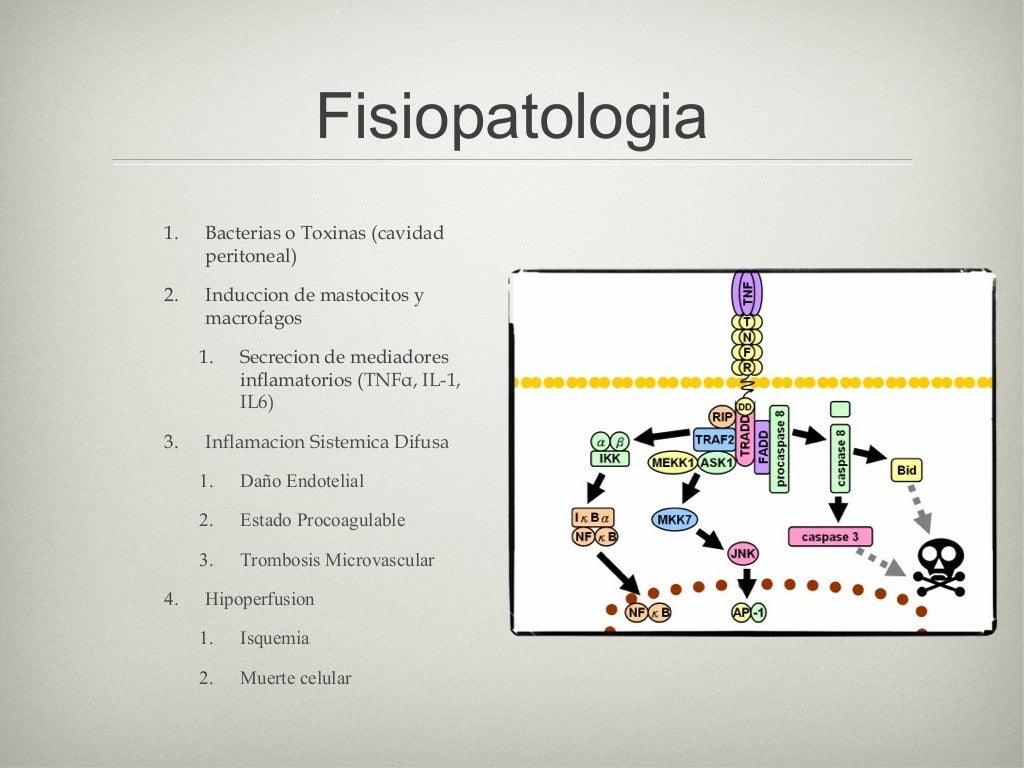

Although sepsis is a systemic process, the pathophysiological cascade of events may vary from region to region.

sepsis abdominal Symptoms specific to the type of infection, such as painful urination from a urinary tract infection or worsening cough from pneumonia. Why does abdominal sepsis occur? Abdominal sepsis represents the host’s systemic. Overview an infection can start with a simple injury—like a shallow cut on the arm—that allows bacteria and other microbes to slip into your body’s tissue or circulation. Severe sepsis and septic shock; Without urgent treatment, it can lead to. What causes abdominal pain in sepsis? Although sepsis is a systemic process, the pathophysiological cascade of events may vary from region to region.